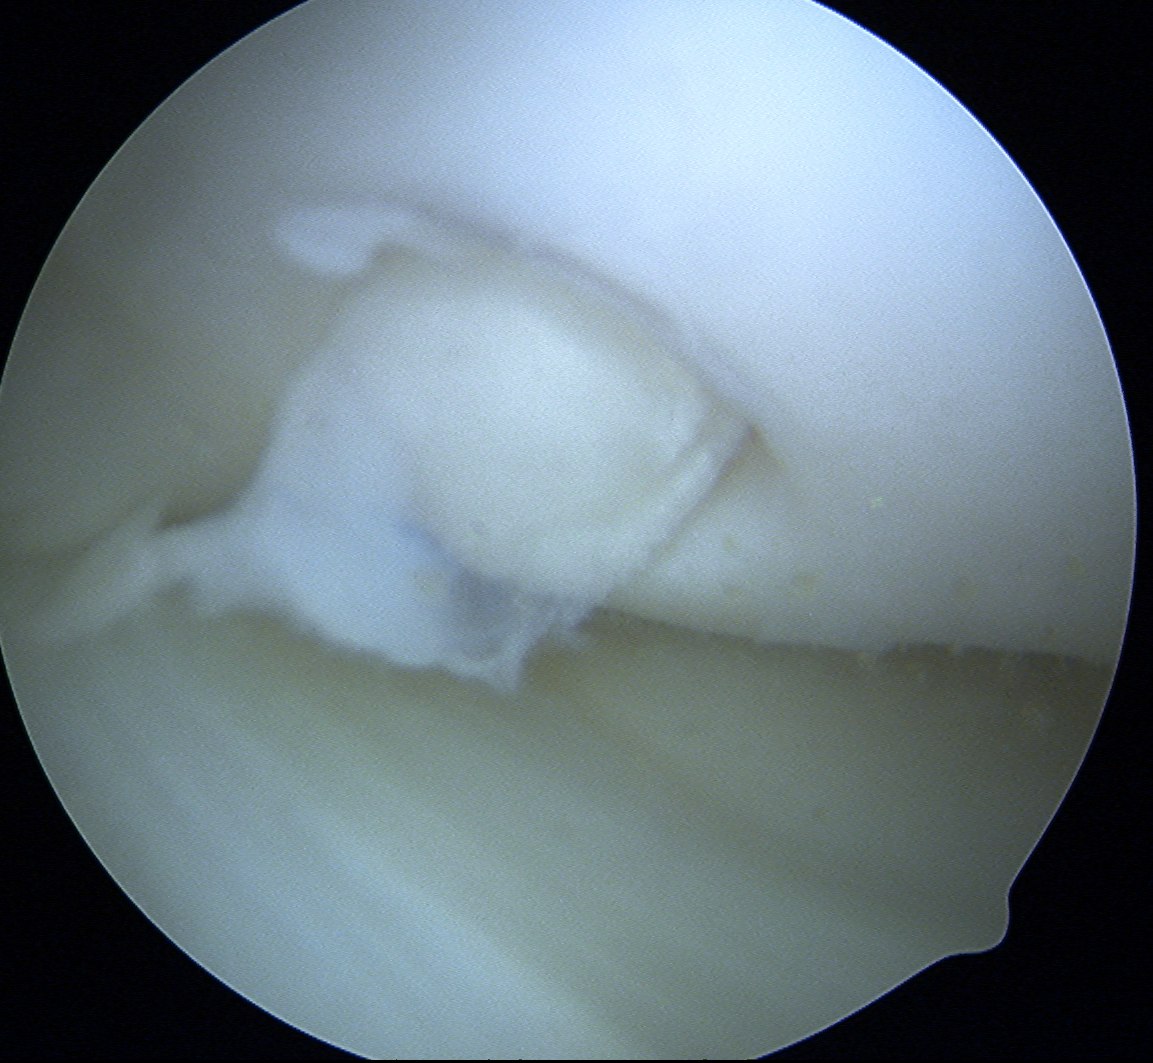

Debride base of OCD and reduce

Drill site of mosaicplasty with 4.5 mm drill

- overdrill 2 - 4 mm

- do not want to leave plug proud

- impossible to sink further or remove